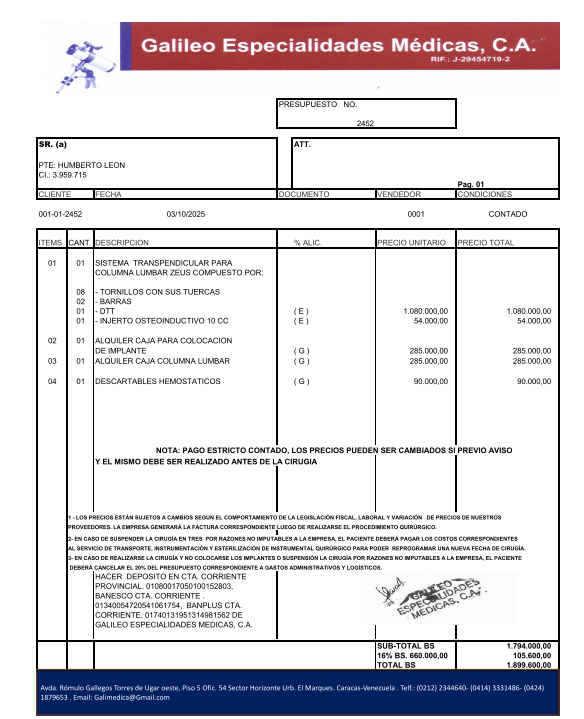

El procedimiento tiene un costo aproximado de 10.000 dólares, más honorarios médicos, fisioterapia, enfermería, exámenes, etc, lo que asciende a más 15.000 dólares, una suma que no tengo yo ni mi familia. Sin embargo, sé que con el apoyo y la solidaridad de muchas personas puedo tener la oportunidad de operarme, aliviar mis dolores y seguramente volver a caminar.

Plan terapéutico: Cirugía propuesta: Abordaje dorsal posterior con fijación mediante tornillos transpediculares (8 tornillos poli-axiales). Colocación de 2 barras de titanio y caja intersomática.Exéresis (retiro) de la lesión tumoral. Pleurostomía (drenaje pleural). Estudio anatomopatológico de tejido óseo obtenido.